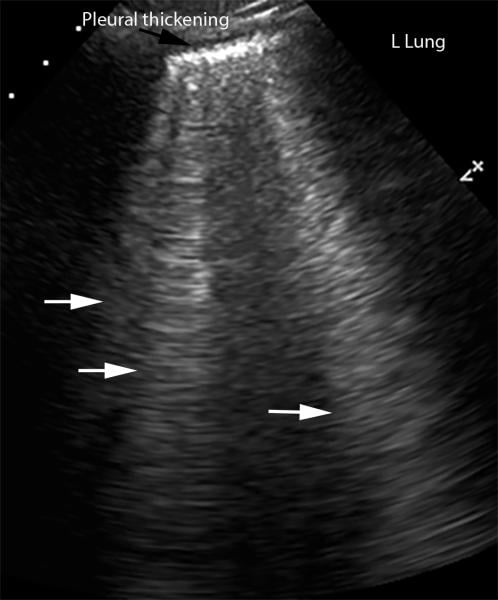

This photo gallery shows the variety of radiological presentations of COVID-19 (SARS-CoV-2) in medical imaging, including computed tomography (CT), radiograph X-rays, ultrasound, echocardiograms and magnetic resonance imaging (MRI). The radiology images show examples of typical COVID pneumonia in the lungs and the numerous complications the virus causes in the body in multiple organs, including the brain, kidneys, heart, abdomen and vascular system.

Ultrasound, especially hand-held ultrasound imaging devices, have become a primary imaging modality for novel coronavirus because of the ease to bag the device and sterilize it after use. CT and mobile X-ray systems are also used as front-line imaging systems for COVID-positive or suspected COVID patients.